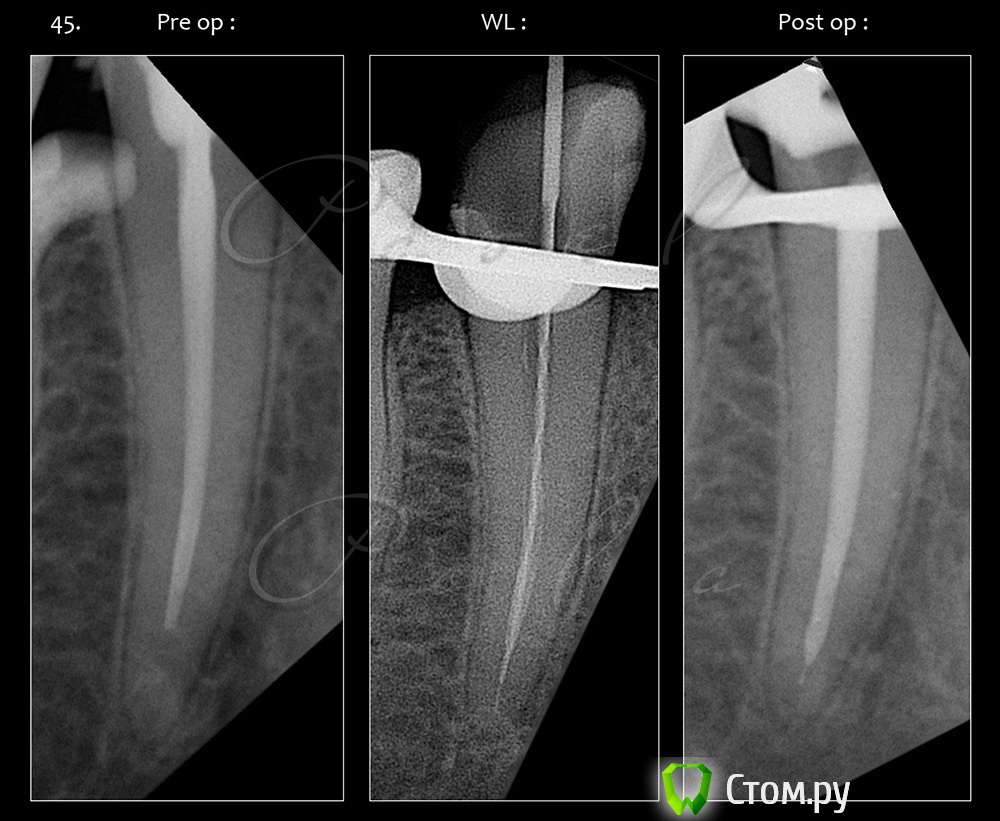

M@estro Опубликовано 14 сентября, 2014 Поделиться Опубликовано 14 сентября, 2014 (изменено) Эндо - ортопедический кейс. До вмешательства : http://s020.radikal.ru/i715/1409/ab/12f0b8206958.jpg 44 : http://s019.radikal.ru/i606/1409/ec/a20e5f3456a6.jpg в два этапа,язычный канал был обтурирован во второе посещение. Этот кейс был опубликован в группе "перелечивания и эндо". Латеральная конденсация. 45 : http://i077.radikal.ru/1409/ae/46e0381ae7eb.jpg Была положительная симптоматика ( перкуссия) , после лечения исчезла. "Patency" не получил. 46 : http://s018.radikal.ru/i520/1409/1a/57ad2b5a48aa.jpg тут стандартная "добыча" . 4.7 витальный. Ортопедия : http://s50.radikal.ru/i129/1409/b5/916fdb8a0ede.jpg http://s019.radikal.ru/i642/1409/82/4c4871c06c06.jpg http://s018.radikal.ru/i523/1409/76/4b62878e182a.jpg Такие дела . Изменено 14 сентября, 2014 пользователем M@estro 14 Ссылка на комментарий